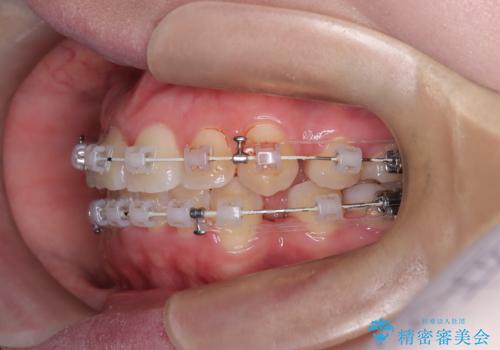

- 患者様は、結婚式までに歯並びを整えたいとのご要望で来院されました。診断の結果、上下左右の第一小臼歯を抜歯し、歯列全体を整える計画としました。審美性を重視し、目立ちにくいホワイトワイヤーを使用した矯正を提案しました。治療期間は2年を目安とし、結婚式までに前歯の整列と噛み合わせを優先的に整えるスケジュールで進めました。定期的な調整と経過観察を通じて、計画的に治療を進めました。

結婚式までに仕上げるため、通常よりも細かく調整を行い、歯の動きを効率的に管理しました。審美ワイヤーを使用したことで、治療中も目立ちにくく、写真撮影などの日常生活での見た目の負担を軽減しました。抜歯部分のスペースを閉じる際には、前歯の位置や噛み合わせのバランスに配慮し、過度な力がかからないよう進めました。患者様の大切なイベントに間に合うよう治療計画を立て、理想的な仕上がりを実現しました。